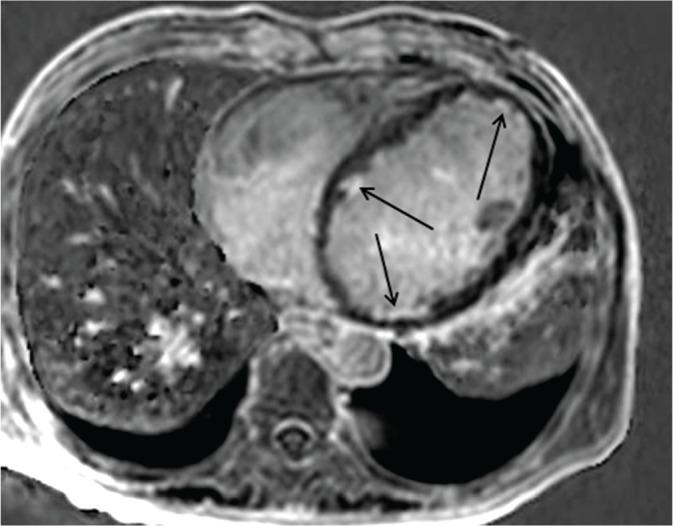

Three-dimensional (3D) cardiac magnetic resonance (MR) imaging has several advantages, including the easy coverage of the entire heart without misregistration, reduction of breath-holding times, and availability for postprocessing reconstruction. These advantages are associated with some techniques such as breath-hold or navigator gating and parallel imaging. However, the image quality of 3D cardiac MR images is compromised by the use of a shorter repetition time and parallel imaging. Thus, a steady-state free precession sequence, contrast agent administration, and presaturation pulses are used to maintain the image quality. In this review, we introduce the MR imaging techniques used in 3D cardiac MR imaging and demonstrate the typical 3D cardiac MR images, followed by discussion about their advantages and disadvantages.

三维(3D)心脏磁共振(MR)成像具有多个优点,包括能够轻松覆盖整个心脏且无配准错误、减少屏气时间以及可用于后处理重建。这些优点与一些技术相关,如屏气或导航门控以及并行成像。然而,使用较短的重复时间和并行成像会损害3D心脏MR图像的质量。因此,采用稳态自由进动序列、造影剂注射和预饱和脉冲来维持图像质量。在本综述中,我们介绍了3D心脏MR成像中使用的MR成像技术,并展示了典型的3D心脏MR图像,随后讨论了它们的优缺点。